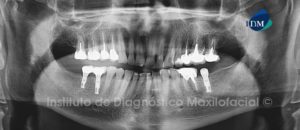

Paciente masculino de 54 años de edad que es referido para el estudio imagenológico previo a la colocación de implantes dentales. A la evaluación de